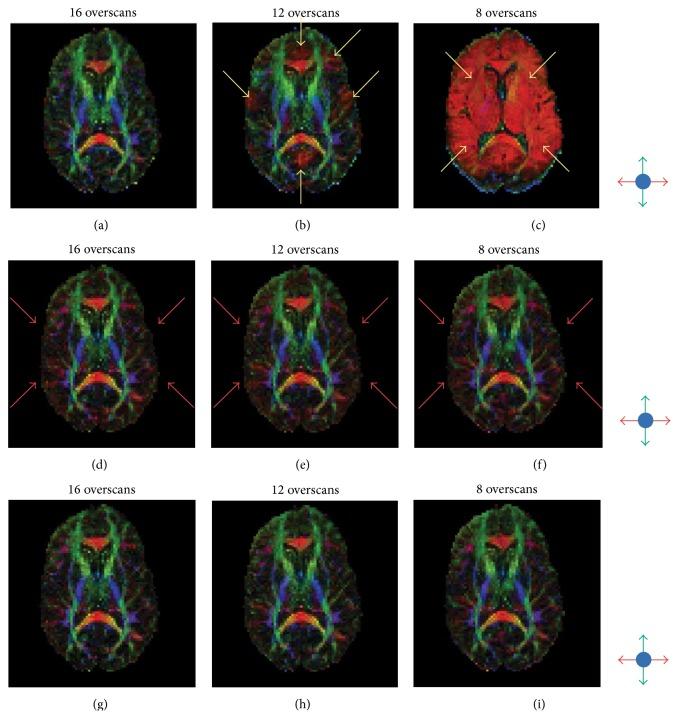

Motion immune diffusion imaging using augmented MUSE for high-resolution multi-shot EPI

“Motion immune diffusion imaging using augmented MUSE for high-resolution multi-shot EPI” authored by Shayan Guhaniyogi et al. has been published in Magnetic Resonance in Medicine.